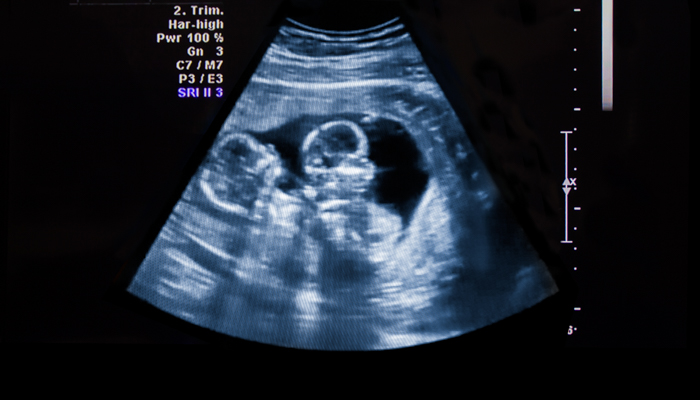

Obstetrics & Gynecology

Brigham and Women's Hospital is where leaders in complex obstetrics and gynecology have been advancing care for over 180 years.